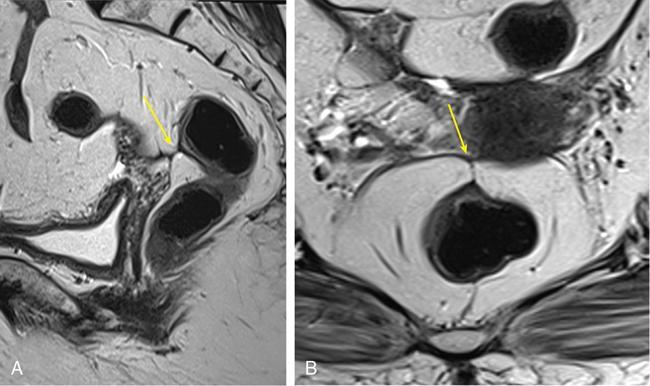

Sumit Mukhopadhyay, Saugata Sen, Aditi Chandra, Argha Chatterjee, Priya Ghosh, Anisha Gehani Cloaca is the part of hindgut caudal to the attachment of the allantoic diverticulum. It divides into a broad anterior urogenital (vesicourethral and urogenital sinus) part and a narrow posterior anorectal compartment/primitive rectum, separated by the urorectal septum. This anorectal compartment gives rise to mid rectum and lower rectum and upper part of anal canal proximal to dentate line. The peritonealized upper part of rectum develops from hindgut proximal to cloaca. The distal most part of anal canal below the dentate line develops from invaginated ectoderm known as proctodeum (Fig. 8.5.1). Initially during development, the rectum is suspended from the posterior abdominal wall by a mesentery, along with the rest of the gut. After completion of rotation of the gut, rectal mesentery fuses with the posterior abdominal wall, majority of rectum becomes retroperitoneal and hindgut mesentery is seen as mesorectum. The artery of the hindgut is inferior mesenteric artery. Anatomically, classically taken as 6 inches (approximately 15 cm), or beginning at the level of S3 vertebra. Surgically defined as 15–18 cm from anal verge (AV), thus anal canal and rectum are considered together for the purpose of surgical and radiological anatomy, though management differs in cases of rectal adenocarcinoma and anal squamous cell carcinoma (SCC). Various trials on rectal cancer neoadjuvant therapy have taken different lengths of cut-off for rectal cancer starting from AV: 9 cm, 12 cm, 15 cm or 16 cm (Table 8.5.1). Rectum continues as sigmoid colon superiorly. The point of transition between rectum and sigmoid colon is controversial. Anatomically, this is the point where sigmoid mesocolon ends, appendices epiploicae are lost and taenia coli gradually converge and disappear. There is no single transition point between these features. These features are not visible to the radiologist/endoscopist as well. Several features defining rectosigmoid junction/transition are variously accepted by different radiologists: Rectum continues as anal canal, which opens to the exterior at AV (mucocutaneous junction). Anorectal junction (ARJ) is considered to be the point at which the angle of the long axis changes, and corresponds to the upper border of puborectalis muscle. The change in axis of anal canal and rectum is well visualized on sagittal MRI. Dentate line lies along the anal crypts (the openings of anal glands), and vertical folds called columns of Morgagni extend superiorly from the dentate line. Anatomists consider the dentate line to be the landmark for ARJ, but the dentate line lies distal to the puborectal sling, and this definition is not clinically relevant. Anal canal is directed posteroinferiorly. At ARJ, the long axis of rectum changes so that it is directed anteroinferiorly. Mid rectum and upper rectum follow the sacral concavity, and the long axis of rectum is again directed posteroinferiorly. Upper rectum is frequently mobile and may not be in midline. Three incomplete folds consisting of mucosa, submucosa and circular muscles, named as Valves of Houston, are seen within the lumen of rectum during endoscopy, but these are not visualized radiologically. The middle valve is roughly at the level of anterior peritoneal reflection, and the superior most valve is at the level of rectosigmoid junction. Surgically and radiologically, rectum is divided into thirds: lower third, middle third and upper third (Table 8.5.2). Most commonly, this division is according to distance or length from AV. Lower third is 0–5 cm, middle third is 5–10 cm, upper third is 10–15 cm from AV (Fig. 8.5.6). Some radiologists define low rectum as 6 cm or less from AV, mid rectum as 7–11 cm and upper rectum as 12–15 cm. The justification of defining low rectum as 6 cm or less from the AV is that, management of most of the tumours at this location suffers from surgical challenges due to tapering of mesorectum and proximity of other pelvic structures. These tumours have a higher rate of CRM positivity, abdomino-perineal resection (APR) and permanent stoma, higher rates of recurrence and mortality, poor function of stoma after sphincter preservation. Another way of defining low rectum, surgical management of which differs from the upper two-thirds, is the portion lying distal to the proximal origin of levators at pelvic side wall. This definition was provided by the English National Low Rectal Cancer Development Programme (LOREC) and is best visualized in the coronal plane by a line joining proximal origins of levators at pelvic side walls (Fig. 8.5.7). ARJ is an important landmark in the management of rectal cancer. Distance between lower border of the tumour and ARJ is important for treatment planning. ARJ is defined as the point at which puborectalis fuses with the levator muscles, and the long axis of rectum changes from anteroinferior to posteroinferior at this point. Its upper extent begins few centimetres above the dentate line, and its length varies from 2–5 cm from AV. Histologically the proximal end of the anal canal is the point at which the columnar epithelium of the rectum becomes the transitional epithelium. Anal canal mucosa has several longitudinal columns, known as anal columns, which end at the dentate line. Below the dentate line the mucosa is smooth and transitions into skin at AV. Approximately at the level of dentate line, the internal anal sphincter (IAS) ends, and the smooth mucosa leads to the intersphincteric plane, distal to which the external anal sphincter extends up to the AV (Fig. 8.5.8). Upper third of rectum is anteriorly covered by peritoneum. Peritoneal covering gradually widens superiorly till it is covered by peritoneum on all sides at the level of sigmoid colon. The exact level of peritoneal reflection varies between individuals, and is quite often seen in axial and sagittal MRI. In axial T2-weighted MRI, a thin hypointense layer with V-shaped attachment to anterior rectal wall is seen representing the anterior peritoneal reflection. This is known as the ‘sea-gull’ sign. Mesorectum and mesorectal fascia (Fig. 8.5.10): lower two-thirds are surrounded by extraperitoneal fat and connective tissue known as mesorectum, which contains lymph nodes, nerves and blood vessels (descending branches of superior rectal artery and corresponding veins). Mesorectal fat is contained within a thin layer of fascia, known as mesorectal fascia (MRF). MRF separates mesorectal fat from extra mesorectal tissues of the pelvis. A relatively avascular plane of areolar tissue lies between MRF and parietal pelvic fascia, facilitating surgery. Importance: Assessment of structures within mesorectum is important for staging and prognostication of rectal cancer. Mesorectal node involvement is N disease. Tumour extension within mesorectal vessels is known as extramural vascular invasion (EMVI) and is thought to be associated with higher chances of vascular dissemination and distant metastases. MRF forms the boundary of the surgical excision plane in total mesorectal excision (TME) – the standard surgery for rectal cancers at present. It is important to understand the various fascial reflections of the pelvis in order to understand pathways of disease spread. The plane between the MRF and the pelvic fascias is the surgical plane. Posteriorly, covering the sacrum, presacral venous plexus and hypogastric nerves, lies the presacral fascia. It fuses with MRF inferiorly at the level of levator ani muscle. The space between presacral fascia and MRF is known as the retrorectal/rectosacral/pelvirectal space, and that between the sacrum and presacral fascia is the presacral space. The presacral fascia continues laterally as the parietal pelvic fascia which covers the lateral pelvic wall. It has two lamellae which encase the pelvic visceral nerves as they course forward from the sacrum to the anterior pelvic organs. The rectosacral fascia/Waldeyer fascia, called as rectosacral ligament by anatomists, is a thickening arising from presacral fascia and running forward to meet the MRF. This divides the rectosacral space into a superior and an inferior compartment, communicating with each other. In males, anteriorly, between the rectum and prostate-seminal vesicles, lies the rectoprostatic fascia/Denonvillier fascia. It is difficult to distinguish from the closely related MRF, and carries the hypogastric nerve and vascular branches to the prostate and male genital organs. In females, anterior to the MRF, lies the rectovaginal septum. According to most views, this septum consists of two layers. The anterior layer corresponds to Denonvillier fascia, and extends from the pelvic floor to the posterior wall of vagina and uterus. The posterior layer is in close relation to the MRF, runs from the pelvic diaphragm and ascends to the peritoneal reflection before fusing with the rectal wall. The lateral rectal ligaments are controversial structures as they are not visualized by imaging and may not carry important structures such as nerves and vessels. However, in some cases, the middle rectal artery may run through them and the accompanying lymphatics may provide a pathway between mesorectal and extra mesorectal lymph nodes. In females, the pelvic floor may be considered to have three compartments, anterior compartment containing bladder and urethra, middle compartment containing the vagina and the posterior compartment containing the rectum. These compartments are supported by the endopelvic fascia and levator ani muscle. The levator ani has several compartments, of which the two most important ones are the iliococcygeus and puborectalis. The iliococcygeus starts as the same fibres as the EAS, and then fans out as a sheet to insert at the pelvic sidewall at the tendinous arch. Posteriorly these fibres fuse in the midline to form the levator plate/raphe. The pubococcygeus and puborectalis are considered together as pubovisceralis muscle. It inserts lateral to the symphysis pubis anteriorly, and forms a sling around the rectum, pulling it anteriorly. Components of the levator ani can be identified in T2-weighted MR images. In males, there are two compartments, anterior containing bladder, urethra, prostate and seminal vesicles and the posterior compartment containing the rectum. Pubococcygeus consists of pubourethralis and puborectalis in males. In sagittal images, the pubococcygeal line is an important reference line, drawn from the inferior border of symphysis pubis to the last joint of the coccyx, representing the level of pelvic floor. The H line is drawn from the inferior aspect of the symphysis pubis to the posterior wall of the rectum at the level of ARJ. This represents the anteroposterior width of the levator hiatus, and upper limit of normal is 5 cm. The M line is the vertical descent of the levator hiatus, drawn as a perpendicular line dropped from the pubococcygeal line to the posteriormost aspect of the H line, and should measure maximum 2 cm. The angle of the levator plate and the pubococcygeal line is also measured. In axial images, the entire normal levator is of uniform thickness and homogeneous low signal intensity. Coronal images show intact iliococcygeus muscle which is convex upwards. The upper half of the anal canal proximal to the pectinate line, the IAS, the conjoint longitudinal coat and the rectum drain lymph upwards into the mesorectal nodes (Fig. 8.5.11) and then lymphatics follow the superior rectal artery into the inferior mesenteric group of lymph nodes. The lymph from these nodes is carried by the intestinal lymph trunk(s). Anal canal below the dentate line along with the EAS drains to the superficial inguinal nodes. Lymphatic vessels also travel with the median sacral artery and drain the puborectalis muscle before finally joining the internal iliac lymph nodes. The internal iliac lymph nodes drain into pre-aortic and paraaortic (lumbar) lymph nodes and efferents from the nodes form the lumbar trunks. The intestinal trunks and the lumbar trunks enter the abdominal confluence of the lymph trunks at the level of the L1–L2 vertebrae, called the cisterna chyli, and then ascend as the thoracic duct. The pelvic lymph nodes lying outside the mesorectum are termed as ‘extra mesorectal lymph nodes’. Above the dentate line: blood supply is from the superior rectal artery, which originates from the inferior mesenteric artery, a branch of abdominal aorta. Superior rectal artery passes in the sigmoid mesocolon and divides into two branches behind the rectum at the level of S3 sacral segment. The superior rectal artery ends in the anal columns by forming a rich vascular plexus/anastomosis with the branches of inferior rectal artery. Blood returns via the superior rectal veins into the inferior mesenteric vein, which drains into the splenic vein and eventually into the portal venous system. Below the dentate line, the inferior anal canal obtains its blood supply from the inferior rectal artery, which is a branch of internal pudendal artery, originating from the anterior division of internal iliac artery. Blood returns via the inferior rectal vein, which drains into internal pudendal veins, internal iliac veins and ultimately into the inferior vena cava (systemic circulation). Thus anal canal is a site of portosystemic anastomosis. Due to the venous anastomoses that occur in the anal canal and the backup of blood flow into the rectal veins, haemorrhoids may be present in patients with portal hypertension. A small part of muscular wall of rectum and anal canal is also supplied by median sacral artery, a direct branch of abdominal aorta arising at the bifurcation of aorta. Nerve supply: The inferior hypogastric plexus lies laterally on the surface of MRF on both sides. It receives sympathetic nerve fibres from the superior hypogastric nerves and parasympathetic ‘nervi erigentes’ from the laterally situated sacral nerves (S2–S4). Laterally, inferior rectal branches of the pudendal nerves and internal pudendal arteries cross the ischio-anal fossa to supply the external sphincter and anal mucosa. T2-weighted small FOV images reveal the layers of rectal wall and details of perirectal soft tissue and pelvic floor most accurately. For adequate assessment of the integrity and involvement of different layers, axial images are needed, which should be obtained perpendicular to the axis of the rectum in that segment. Angle of acquisition should be altered according to the change in axis of rectum (Fig. 8.5.12). The layers of rectal wall from inside to outside are (Fig. 8.5.10): When examining the anorectum with a radial scanning echoendoscope, the internal and EASs can be seen as two distinct rings. The inner hypoechoic ring of tissue represents the IAS the outer hyperechoic tissue ring represents the EAS. The thickness of normal IAS is 2–3 mm, and for EAS: 7–9 mm. The IAS becomes thicker and more hyperechoic with age, while the EAS tends to become thinner with age. Endoscopically, rectum begins at the dentate line and extends to 15–20 cm from the AV. The normal five-layer appearance of rectal wall in EUS is as follows: Imaging in the rectum and anal canal region is mainly for staging of tumours. The most common neoplasm of this region is rectal cancer and preoperative imaging evaluation is required not only for staging early and advanced disease but also for assessing response to treatment and for surgical planning. The techniques described here will mainly pertain to rectal and anal neoplasms. Plain radiographs have a limited role in the evaluation of rectal neoplasms. Primarily, it may be used as a modality in the emergency setting when patients come with constricting colorectal strictures causing large bowel obstruction. Radiographs of the abdomen in supine and erect positions are performed to look for features of bowel obstruction, air-fluid levels and free air under the domes of diaphragm in case of perforation, respectively. Conventional luminal contrast study is now obsolete for diagnosis of tumours in the rectum and anal canal and have been replaced by cross-sectional imaging. Sinogram studies with diluted iodinated contrast have been performed to detect extent of rectal fistulae. Endorectal Ultrasound (ERUS) can differentiate between the layers of the rectal wall and helps detect and stage tumours within the different layers of the rectum. ERUS can view the rectal mucosa in 360 degrees. The layers visualized include rectal mucosa, muscularis mucosa, submucosa, muscularis propria and area between the muscularis propria and perirectal fat. The role of ERUS in rectum is primarily in staging and in posttreatment surveillance of rectal adenocarcinoma. Staging of early tumours requires an ERUS due to its superior diagnostic performance for differentiating T1 from T2 tumours in comparison to other cross-sectional imaging modalities like MRI. As far as surveillance is concerned, endoscopy is mandated as it can detect early asymptomatic recurrences which improves overall survival (OS). This is substantiated by multiple recent meta-analyses in literature. Hence, even for patients on ‘watchful waiting’ as a treatment option after chemoradiotherapy, it is imperative to perform a DRE, EUS, CEA and correlate the findings with restaging MRI. The various recommendations for postoperative surveillance for rectal cancer using endoscopy are enumerated in Table 8.5.3. ASCO: American society of clinical oncology; ESMO: European society for medical oncology; NCCN: National comprehensive cancer network; USMSTF: United States Multi-Society Task Force. Drawbacks include heterogeneity in operator skill and operator dependency as well as inability to pass stenosing lesions. Poor depth of penetration of the probe results in reduced visualization of the mesorectal fat, limited assessment of pelvic side walls and EMVI and reduced diagnostic accuracy for asserting involvement of CRM. Multidetector CT (MDCT) is the primary imaging modality used for rapid evaluation of not only bowel pathologies (luminal or mural) but also for evaluation of surrounding structures such as vessels, lymph nodes and mesentery. The ability to obtain high-quality clinical images through multiplanar reconstructions make it one of the most robust examinations for the initial evaluation of most bowel related pathologies. A routine abdominal CT scan would include acquiring a noncontrast axial image, followed by a portal phase image (at 70–90 seconds). However, for more detailed evaluation of solid organs, a general imaging dataset would include an unenhanced CT, followed by arterial phase (20–30 seconds), portal venous phase (70–90 seconds) and a delayed phase at 3 minutes. Many centres around the world omit the noncontrast scan to reduce radiation exposure. Lesions such as large tumours, pelvic nodes, collections and diverticulosis can be detected by contrast-enhanced CT. CT provides a more holistic evaluation and demonstrates possible complications of tumours such as obstruction, transition point and perforation that may not be clinically evident. However, accurate detection and staging of tumours in the rectum is better performed by MRI. Like TRUS, MRI can depict the layers of the rectal wall with high resolution, especially when performed at 3 Tesla and with an endorectal coil. Although use of endorectal coils may provide improved diagnostic accuracy for T stage as compared with phased-array coils alone, it is known that endorectal coils increase patient discomfort and may account for increasing motion artifacts. Insertion of such coils is also not possible in case of stricturous lesions. Performance of high-resolution imaging using phased-array MRI coils at 1.5 or 3 Tesla, as was used in multicentre trials was excellent. MRI technique and image quality play a critical role in evaluation of rectal cancers, and accuracy is dependent on obtaining high-resolution images that are perpendicular to the plane of the tumour. Particular note is to be made whether the tumour is mucinous or nonmucinous as the former have worse prognosis and higher tendency to metastasize. For technical aspects of MRI, it is recommended by ESGAR that bowels and bladder are emptied. Rectal distension is not indicated as it stretches out the CRM. Minimum slice thickness for such scans is 3 mm. DWI is essential for both primary staging and restaging. Microenemas may be considered to remove air from the rectum and reduce artifacts in DXI sequence. High-risk MRI features for distant metastases include EMVI, mesorectal tumour depth >5 mm, T4 stage, involved circumferential resection margin (CRM). In addition to initial staging prognostic features, MRI also helps in assessing response to neoadjuvant therapy which is also an indicator of survival and chances of recurrence. MRI is sensitive in detecting the presence of lymph nodes but remains nonspecific for differentiation malignant from benign nodes with high diagnostic certainty owing to the presence of micrometastasis even in small-sized nodes (up to 5 mm). Contrast administration is not recommended. Drawbacks of MRI include reduced diagnostic accuracy for identifying early rectal T1 and T2 tumours, and to sometimes differentiate T2 from early T3 lesions. Increased scan times in the elderly and cost may also be constraints in some settings. Virtual colonoscopy can help in identifying primary and synchronous colonic lesions. CT Colonography (CTC) is beneficial after incomplete colonoscopy (due to nonpassable stricture) to evaluate the remainder of the colon. CTC is advocated as a screening test for colonic polyps and colon cancer in vulnerable populations. It has a sensitivity of 93% and a specificity of 97% for detecting polyps >1 cm. MRI scores over all modalities in the local staging of rectal neoplasms. The more common application of PET-CT is in identifying nodal and distant metastases in rectal adenocarcinoma, melanoma and lymphoma. Limitations of PET include poor sensitivity in detecting small (<10 mm) colonic lesions and decreased fluorine-18-2-fluoro-2-deoxy-D-glucose uptake by mucinous tumours. For rectal melanoma, MRI may be performed along with a whole body PET-CT scan for regional and overall staging. Rectal lymphoma does not require local staging and a whole body PET-CT is generally acceptable as the imaging modality of choice. MRI is the imaging modality of choice due to better delineation of the extent and involvement of the anal sphincters. The inguinal nodes are regional nodes in anal cancer and this region is covered in the scan. The most common rectal tumour is rectal cancer. It is also one of the most common malignant neoplasms and the second most frequent cancer occurring in the large bowel. Majority of the patients are in the fifth to seventh decade. However, the incidence of rectal cancer has been on a rise in the younger population. Adenocarcinoma is the commonest histopathologic type of rectal cancer. Other than adenocarcinoma, several other neoplastic lesions also occur in the rectum, but are relatively uncommon (Table 8.5.4). Diagnosis of rectal cancer begins with physical examination/DRE followed by colonoscopy/sigmoidoscopy and biopsy from the mass (see figure below). If malignancy is confirmed on histopathological examination, imaging for staging is ordered (Fig. 8.5.14). MRI is the preferred method for locoregional staging. During staging of early tumours, ERUS also plays an important role. Majority of the guidelines (SAR and ESGAR) accept MRI as the modality of choice for locoregional staging and restaging after neoadjuvant treatment. CT thorax and abdomen is performed for metastatic evaluation. PET-CT is not routinely recommended in metastatic evaluation. ESMO guidelines outline the following indications for PET-CT: (1) If carcino-embryonic antigen (CEA) is high on presentation (2) Extensive EMVI. MRI of the liver may be recommended to evaluate any suspicious or equivocal lesions that are detected on CT scan. Therefore routinely pelvic MRI for locoregional evaluation and CT thorax and abdomen for metastatic evaluation is performed (Table 8.5.5). Based on the investigations, the rectal cancer is staged according to the latest AJCC classification (Table 8.5.6). T0 No evidence of primary tumour Tis Carcinoma in situ T1 Tumour invades submucosa T2 Tumour invades muscularis propria T3 a b c d Tumour invades subserosal tissue and perirectal tissue a <1 mm b 1–5 mm c >5–15 mm d >15 mm T4 a b Tumour invades peritoneum or other organs Tumour penetrates visceral peritoneum Tumour invades other adjacent organs or structures NX Regional lymph nodes cannot be assessed N0 No regional lymph node metastasis N1 a b c Regional lymph node metastasis (1–3 nodes) 1 lymph node 2–3 lymph nodes Tumour deposits in subserosa, mesentery/nonperitonealized perirectal tissues (cannot be differentiated from nodes on imaging) N2 a b Regional lymph node metastasis (>4 nodes) 4–6 node >7 nodes M0 No distant metastasis M1 a B c Distant metastasis Metastasis in one (1) organ Metastasis in more than one organ Metastasis to the peritoneum with/without other organ involvement Once the diagnosis is confirmed and staging investigations are completed, management is usually decided in multidisciplinary team meetings consisting of Surgeon, Radiation oncologist, Medical oncologist, Pathologist and Radiologist. The treatment protocols differ in the United States and Europe (Fig. 8.5.15). The different types of rectal surgeries are enumerated in the Table 8.5.7 and depicted in Fig. 8.5.16. Concept of use of neoadjuvant short course RT, long course RT with chemotherapy and chemotherapy only is a rapidly evolving field. Radiologist should be aware of the protocol used in their institution. A subset of patients (10%–23%) was found to have complete pathological response (pCR) in the postsurgical pathological specimen. There is significant evidence of prediction of pCR on presurgical MRI. Considering the ability of MRI in prediction of pCR, Prof. Habr-Gama and her group suggested the possibility of organ preservation in these patients. Hence ‘watch and wait’ policy came into vogue. In the subgroup where MRI predicts complete response, surgery can be avoided and patients may be followed up every 8–12 weeks using DRE, proctoscopy/sigmoidoscopy and MRI. Both T2W and DWI are used in MRI for prediction of complete response as well as for follow-up for prediction of recurrence. Close follow using the above-mentioned protocol ensures early detection of recurrence and hence treatment. Thus, MRI plays an important role in personalized treatment of rectal cancer. MRI plays an important role in rectal cancer management: During initial staging MRI helps in: In restaging after NACT, MRI helps in: Therefore good-quality high-resolution rectal MRI is required for accurate locoregional staging. Technique and protocol of MRI is summarized in the Tables 8.5.8 and 8.5.9. 1.5T-3.0T magnet strength High resolution T2w sequences Small FOV images Axial and coronal images – parallel and perpendicular to the rectal tumour For low rectal tumours coronal images –perpendicular to the anal canal